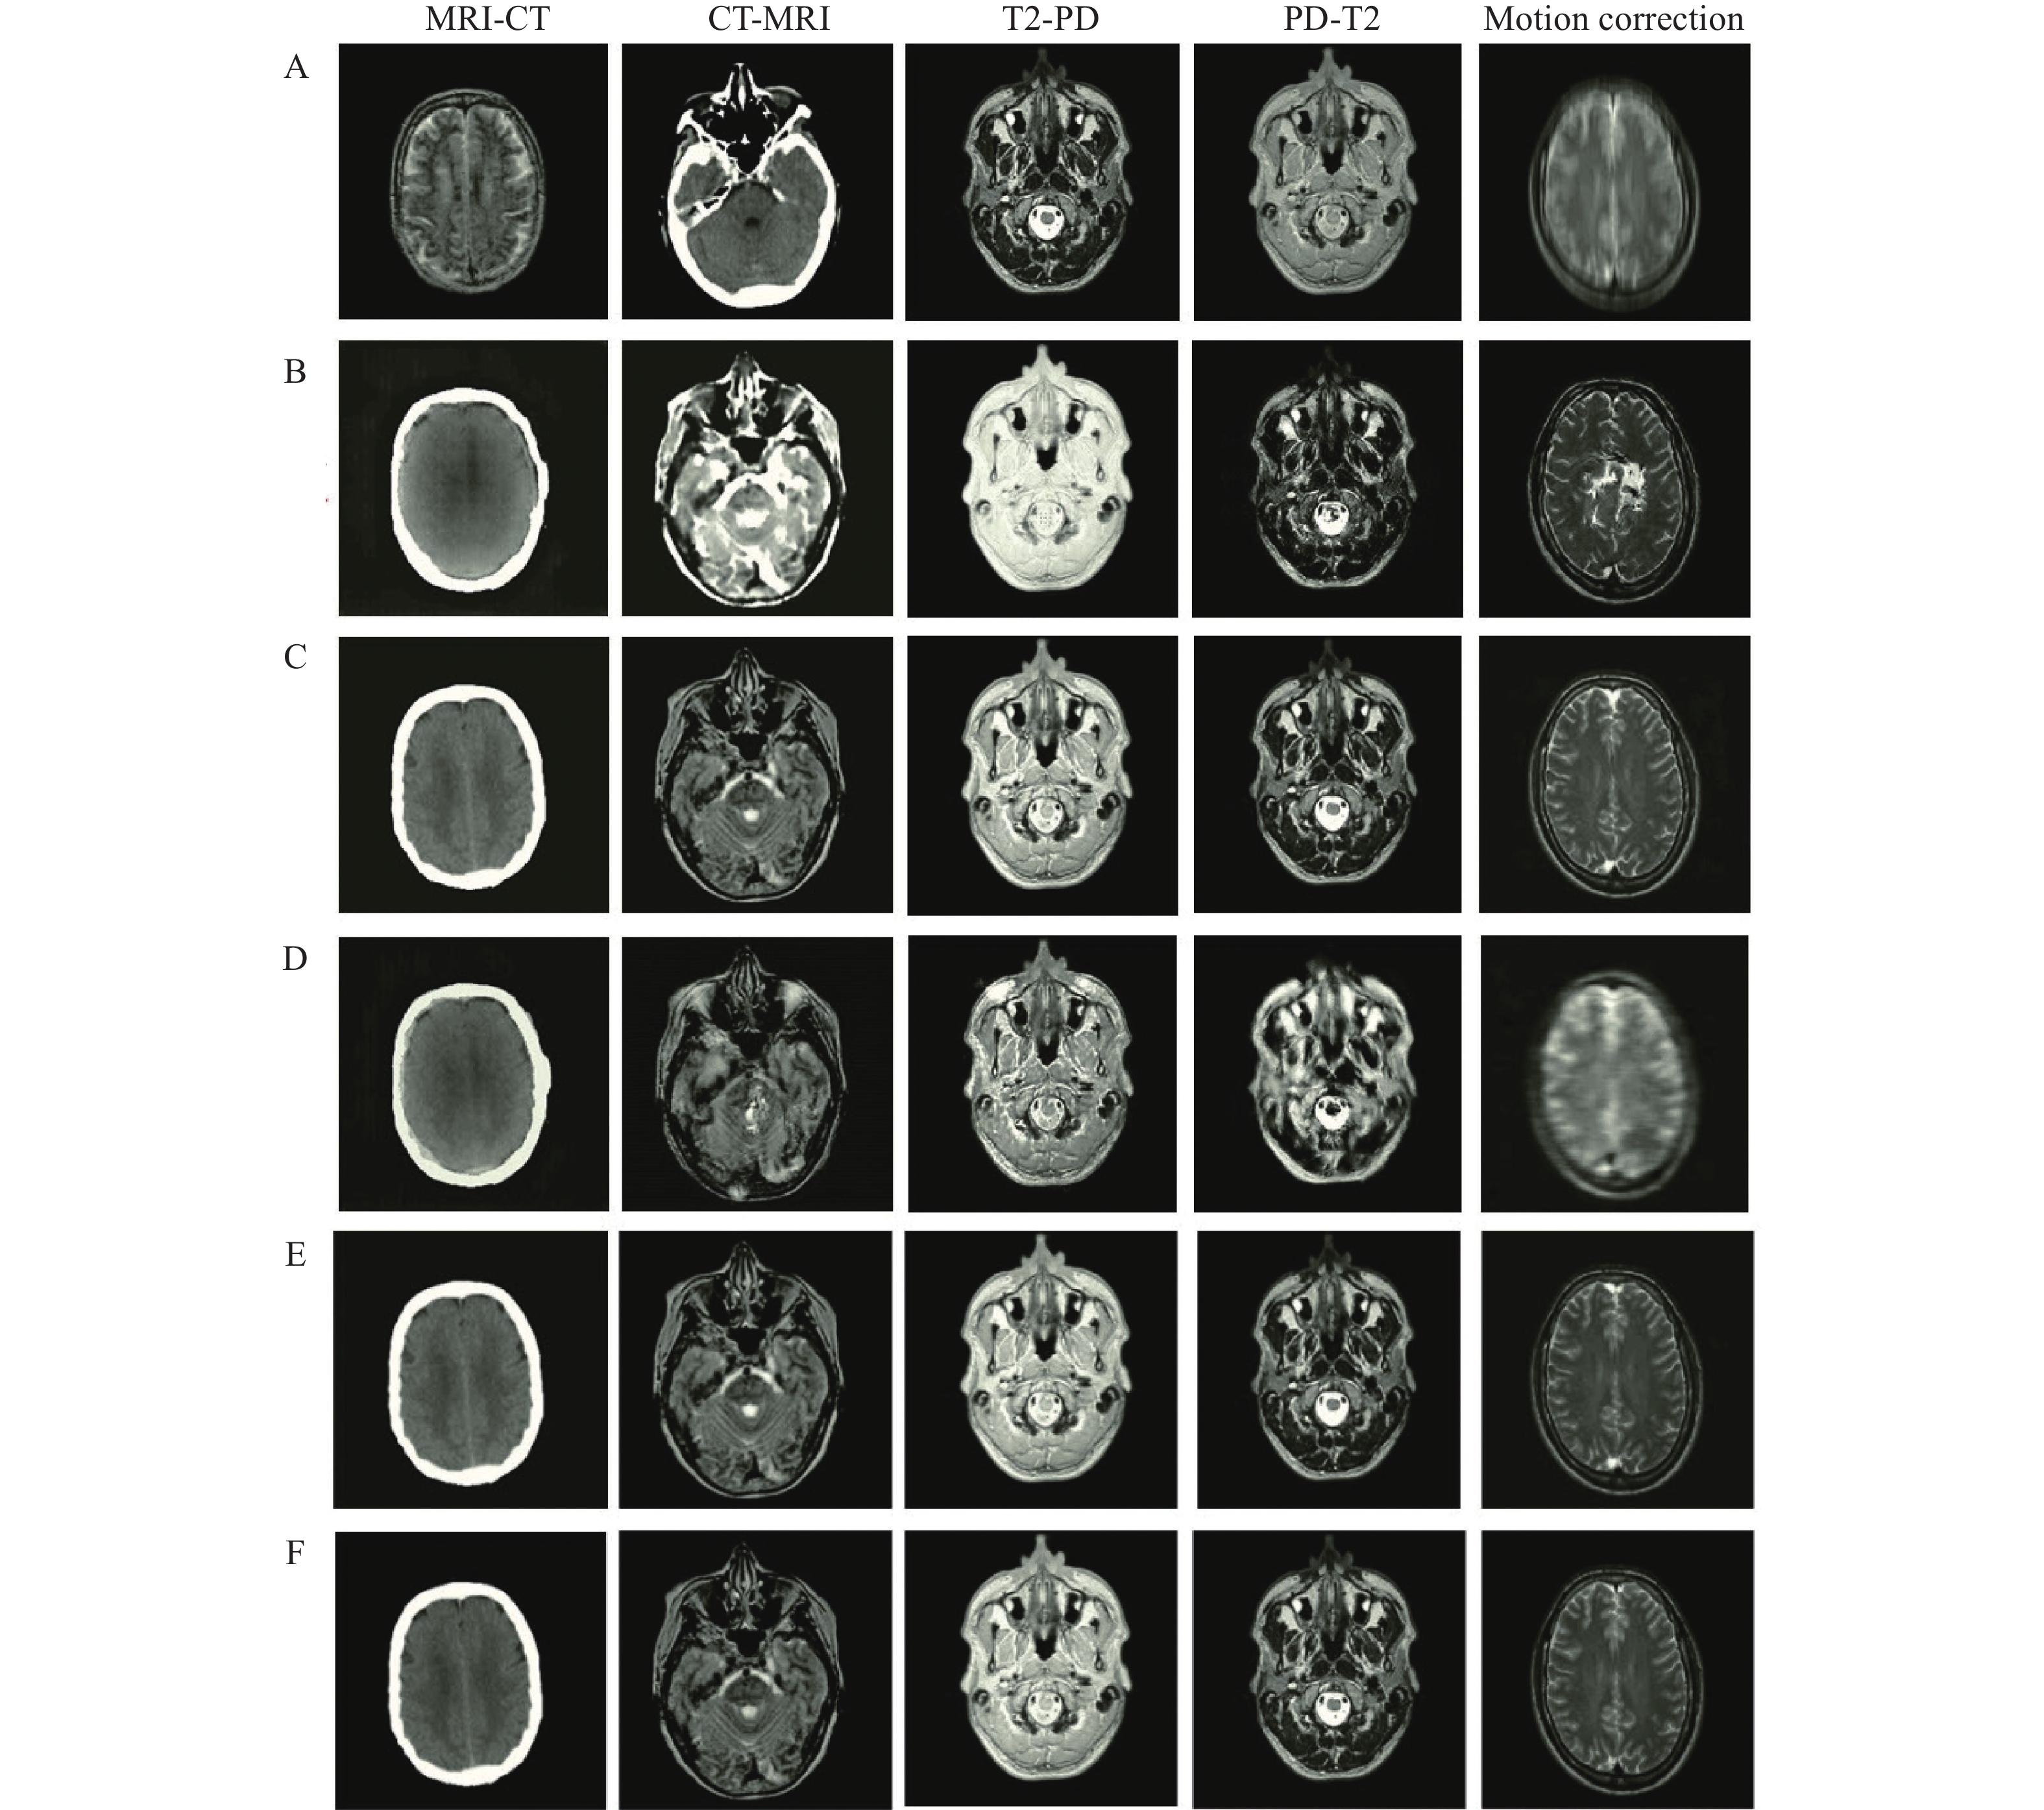

In this section, the results from the proposed encoder-decoder network under different scenarios are presented. Four challenging image-to-image translations including CT-MRI, MRI-CT, T2-PD, and PD-T2 are selected. In the T2-PD and PD-T2 translation, the imaging modality is the same, and the acquired contrast values are different because of the procedure of data collection. At the same time, in the CT-MRI and MRI-CT translations, the imaging modality of the data is different, which makes the issue more difficult and challenging. Additionally, the proposed network is utilized for eliminating motion effects from the medical MR images and translating these into corresponding motion-free images.

The number of epochs, batch size, momentum, and learning rate for the proposed encoder-decoder network in these tasks are considered to be 100, 2, 0.9, and 10−4, respectively. The performance of the proposed network is evaluated and compared with several well-known networks including CycleGAN[19], uncertainty-guided progressive generative adversarial network (UPGAN)[14], registration generative adversarial network (RegGAN)[30], and Pix2Pix[22]. It should be noted that the number of epochs are learning rate are selected by cross validation. The performance is analyzed on the five mentioned tasks (MRI-CT, CT-MRI, T2-PD, PD-T2, and Motion correction). In this regard, different numbers of epoch in the set (20, 40, ···, 100) and learning rates in the set (10−5, 5×10−5, 10−4, 5×10−4, 10−3) are investigated. The result of image-to-image translations using the proposed network and other mentioned networks in different tasks is represented in Fig. 6. The results of the mentioned criteria are reported in Table 1.

According to Fig. 6, the edges and structure of the obtained results using the Pix2Pix and CycleGAN networks are different from the reference data, which indicates an inability of these networks to retrieve boundary and structural information. Additionally, the achieved intensity values using CycleGAN and RegGAN are very different from reference data. Although the obtained results of UPGAN are relatively suitable for different tasks, their quality and sharpness are lower than those in the proposed network. Employing the global-to-local feature fusion strategy significantly improves the structure of results. Using a loss function also emphasizes edges which improves the sharpness and quality of tissue boundaries (Fig. 6).

The evaluation (Table 1) highlighted a better performance of the proposed encoder-decoder network across all criteria. Of course, during image translation MRI-CT and CT-MRI, inputs and outputs belong to different domains. However, for T2-PD and PD-T2, the inputs and outputs belong to the same domain and the recorded intensity values are different. The translation between two different domains (MRI-CT and CT-MRI) is much more challenging than the conversion of intensity values used in T2-PD and PD-T2. The effect of this can be observed in the results of the UPGAN, CycleGAN, RegGAN, and Pix2Pix modeling (Table 1).

In the results obtained from the proposed network, translations between two different domains are not significantly reduced compared to the translation of intensity values. This is due to the power structure of the proposed network in feature extraction, feature integration, and data retrieval. It should be noted that the higher the values for ERMSE and EMAE, the greater the error of the obtained results. Likewise, the higher the values for EPSNR and ESSIM, the greater the accuracy of the results obtained.